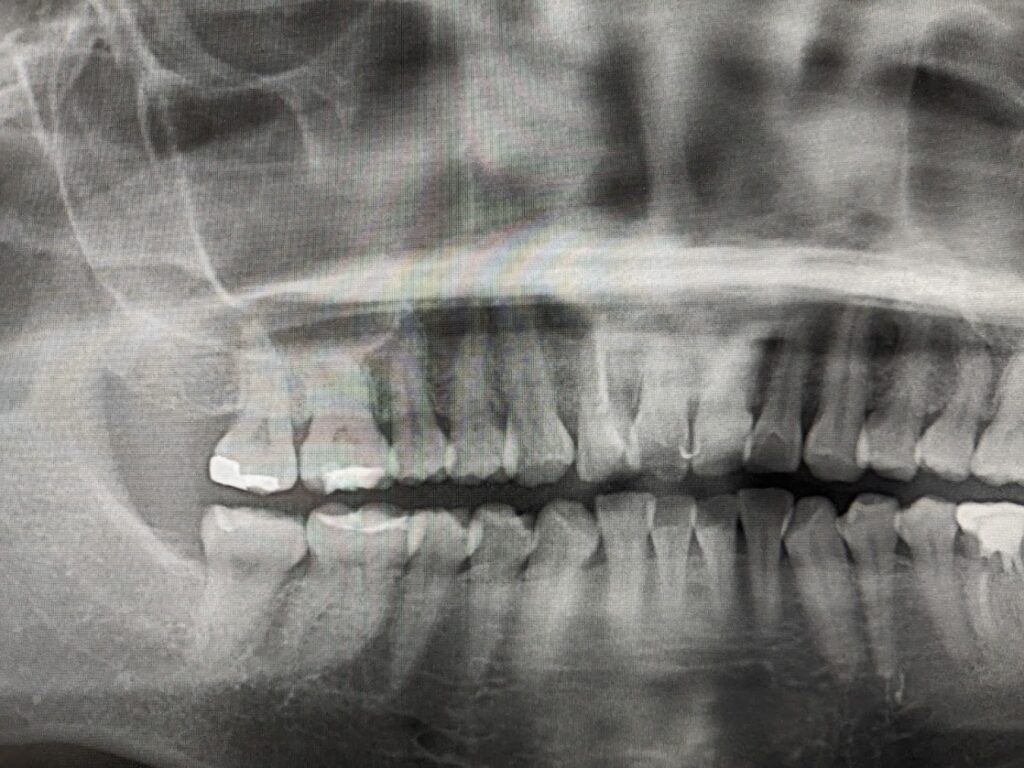

右上2の根管内には白い不透過像を認め根管充填されています。根尖部の透過像をみとめ頬側に膨隆を認める事からCTにて精査を実施することとしました。